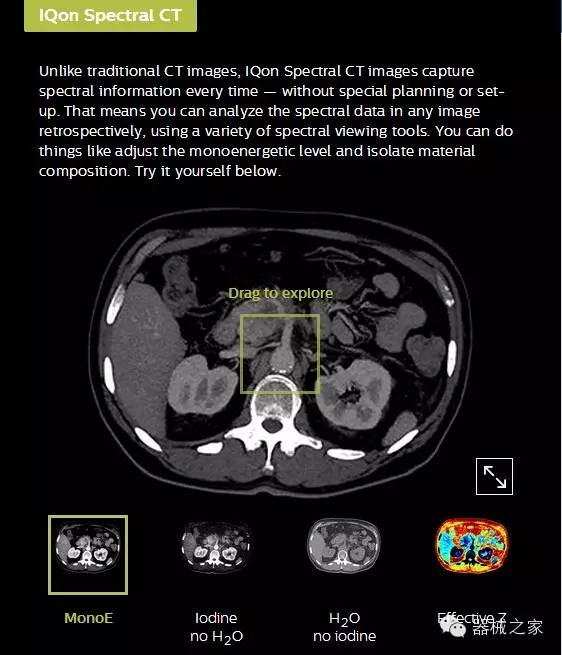

IQon光譜CT能夠按照需求提供光譜量化和工具,并能通過(guò)簡(jiǎn)單工作流程、在低劑量下對結構進(jìn)行定性分析

IQon光譜CT -- 是業(yè)界首臺以探測器為成像基礎的光譜CT,它可以在單次常規掃描下獲得傳統解剖影像及光譜功能影像。不僅可以提供精準的診斷信息,還可簡(jiǎn)化工作流程、在低劑量下完成定量與定性分析。